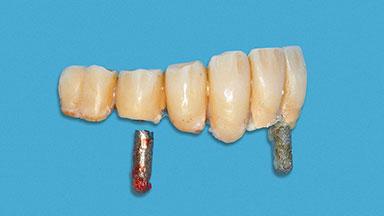

Minimally Invasive Treatment of a Patient in Her Nineties After Removing Implants Affected by Severe Peri-implantitis

A 93-year-old female patient presented in September 2010 with an enlarged swelling on the lingual side of her lower incisors. At the time, she was essentially healthy, except for reduced vision due to bilateral age-related macular degeneration. She had been a heavy smoker (about 30 cigarettes a day) for the past 20 years after becoming a widow. The patient lived at home by herself, with full-time domestic support. An extraoral examination revealed nothing adverse. Intraoral plaque control was anything but ideal, and a soft-tissue tumescence was visible around the lingual aspect of 41–42. Because the nature of the lesion was not clear, a biopsy was carried out that revealed the inflammatory nature of the lesion. The panoramic radiograph showed six irregularly distributed mandibular implants supporting a full-arch prosthesis, with various degrees of interproximal peri-implant resorption. The periapical radiograph revealed interproximal bone resorption mesially and distally to implant 41.